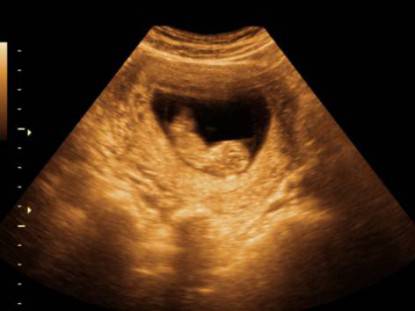

- durante la prima settimana di esistenza dell’embrione ( 4° settimana dal primo giorno della precedente mestruazione) si inizia a formare il sacco gestazionale che accoglie l’embrione e lo protegge fino al termine della gravidanza;

Circa al 60° giorno di vita l’embrione è lungo 1.5 cm e pesa 1 grammo circa,da questo momento si avvia verso la fase successiva in cui si inizia a parlare di feto.